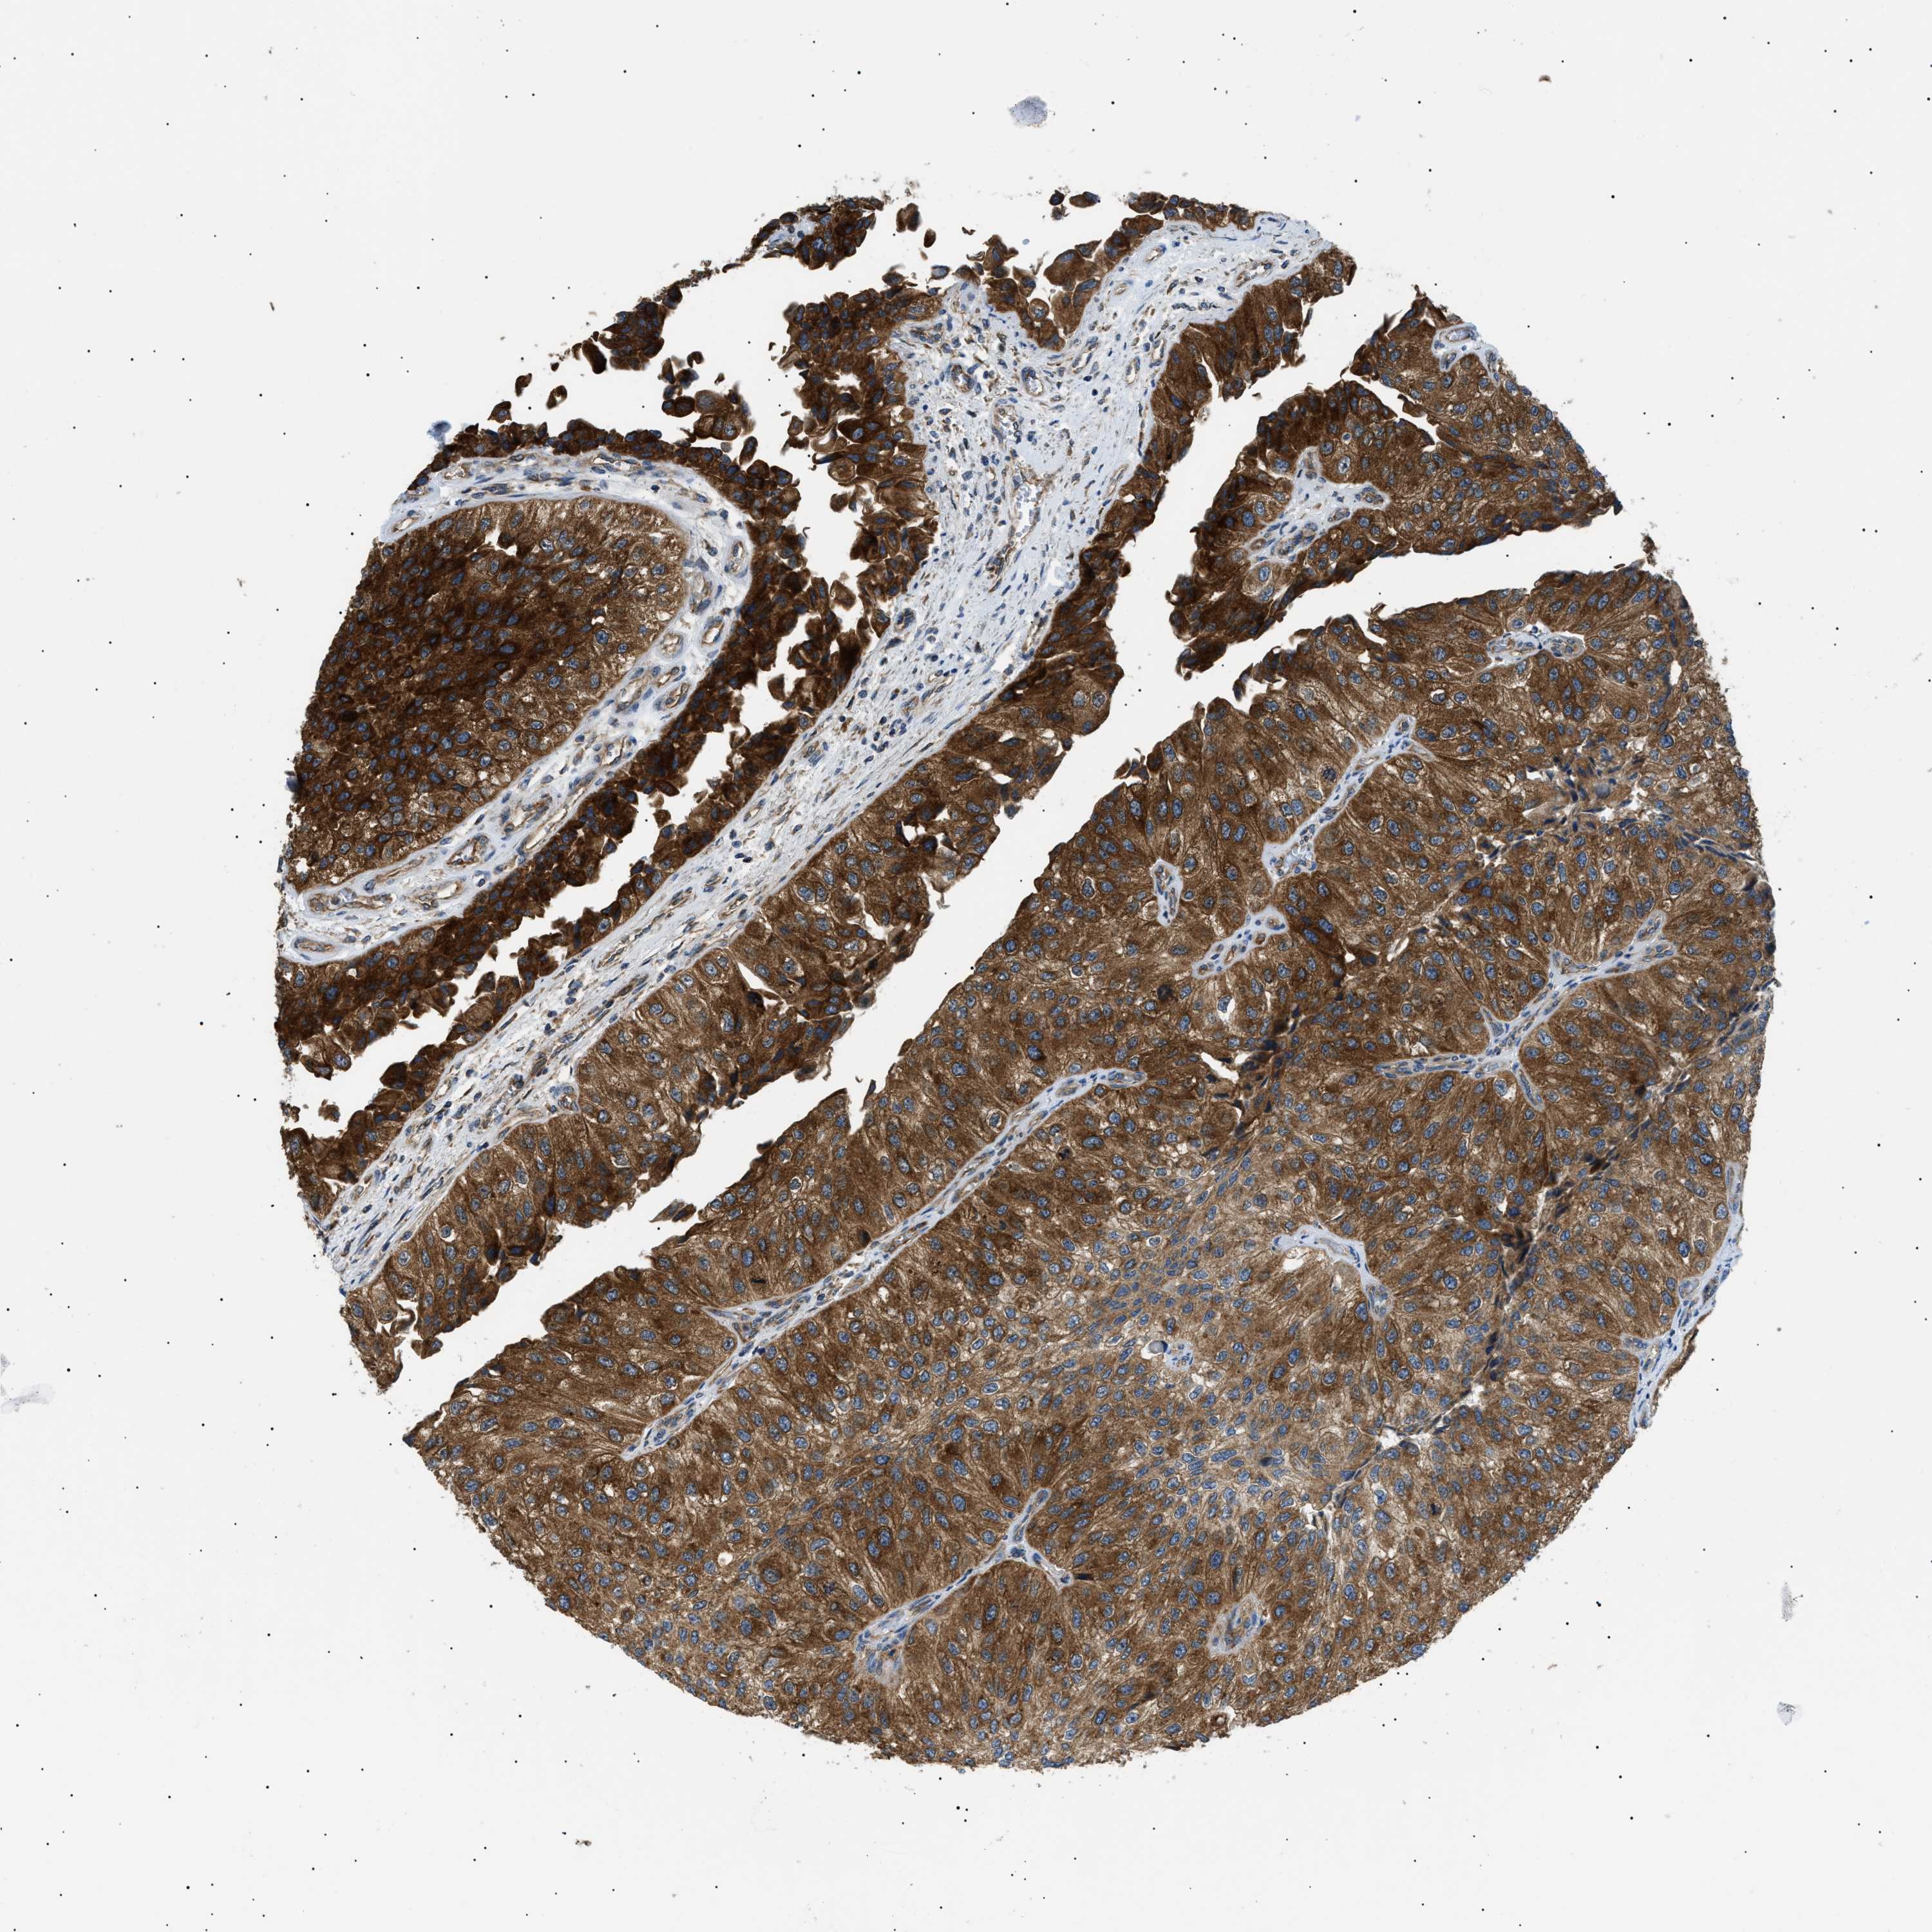

UROTHELIAL CANCER - Protein expressioni

A mouse-over function shows sample information and annotation data. Click on an image to view it in a full screen mode. Samples can be filtered based on level of antibody staining by selecting one or several of the following categories: high, medium, low and not detected. The assay and annotation is described here.

Note that samples used for immunohistochemistry by the Human Protein Atlas do not correspond to samples in the TCGA dataset.

Antibody stainingi

Antibody staining in the annotated cell types in the current human tissue is reported as not detected, low, medium, or high, based on conventional immunohistochemistry profiling in selected tissues. This score is based on the combination of the staining intensity and fraction of stained cells.

Each image is clickable and will lead to virtual microscopy that enables deeper exploration of all samples and also displays staining intensity scores, fraction scores and subcellular localization as well as patient and tissue information for each sample.

Antibody HPA016431

Staining

High

Medium

Low

Not detected

Intensity

Strong

Moderate

Weak

Negative

Quantity

>75%

75%-25%

<25%

None

Location

Nuclear

Cytoplasmic/membranous

Cytoplasmic/membranous,nuclear

Urothelial carcinoma, Low grade

Urothelial carcinoma, High grade